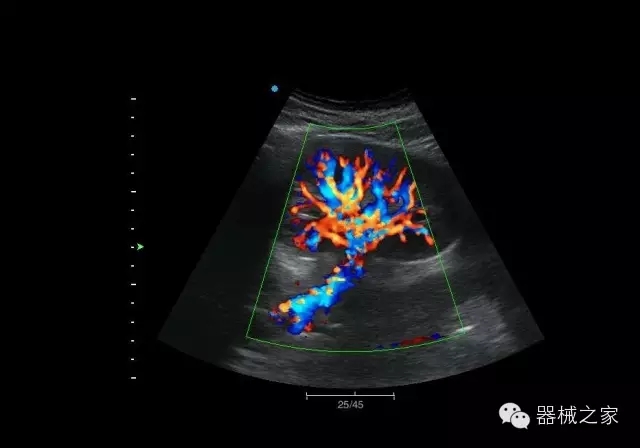

經(jīng)典產(chǎn)品:M7(星鉆)

臨床圖片賞析

產(chǎn)品特點

·裝載有采用Multi-Core多核處理的非嵌入式平臺,成像效率大大提高,并且能夠給用戶帶來高速、多任務(wù)并行信號處理體驗;

·優(yōu)秀的圖像效果、強大的功能體驗、豐富的探頭選擇、合理的便攜式設(shè)計,全中文顯示及病人管理界面,使得M7在任何場合、任何時候都能快速響應(yīng)更好的心血管、腹部、婦產(chǎn)、小器官等常規(guī)超聲檢查以及肌骨、神經(jīng)、顱腦、術(shù)中等新興領(lǐng)域的使用需求;

8倍波束并行處理系統(tǒng)

·在便攜式緊湊平臺上采用更多倍波束并行接收信號處理模式,無論二維還是彩色血流圖像狀態(tài)下,擁有更靈敏的回波頻移捕獲能力,大大提高時間分辨率,尤其使得心血管表現(xiàn)更為突出;

PSHI?寬帶頻移諧波技術(shù)

·在普通組織諧波的基礎(chǔ)上,通過精確控制的波束形成器,發(fā)射兩組具有相位偏差反向的信號,并采用并行信號處理,數(shù)字化合成并采樣回波信號,在高靈敏度的濾波器的處理過程中獲取更純凈的諧波信號,使圖像具有更加出眾的細(xì)節(jié)分辨率;

iClear®+iBeam?

·智能化按線復(fù)合多角度獲取聲束的原始信號,配合智能化的斑點噪聲識別及控制處理技術(shù),整體提高組織結(jié)構(gòu)細(xì)節(jié)分辨率,任何時候都能快速響應(yīng),更好的滿足心血管的使用需求;

支持全新3T工藝探頭群

·包括探頭材料、結(jié)構(gòu)設(shè)計、加工工藝三方面的革新技術(shù)給圖像帶來品質(zhì)的飛躍;

CFDA注冊證編號

·粵食藥監(jiān)械(準(zhǔn))字20132230475